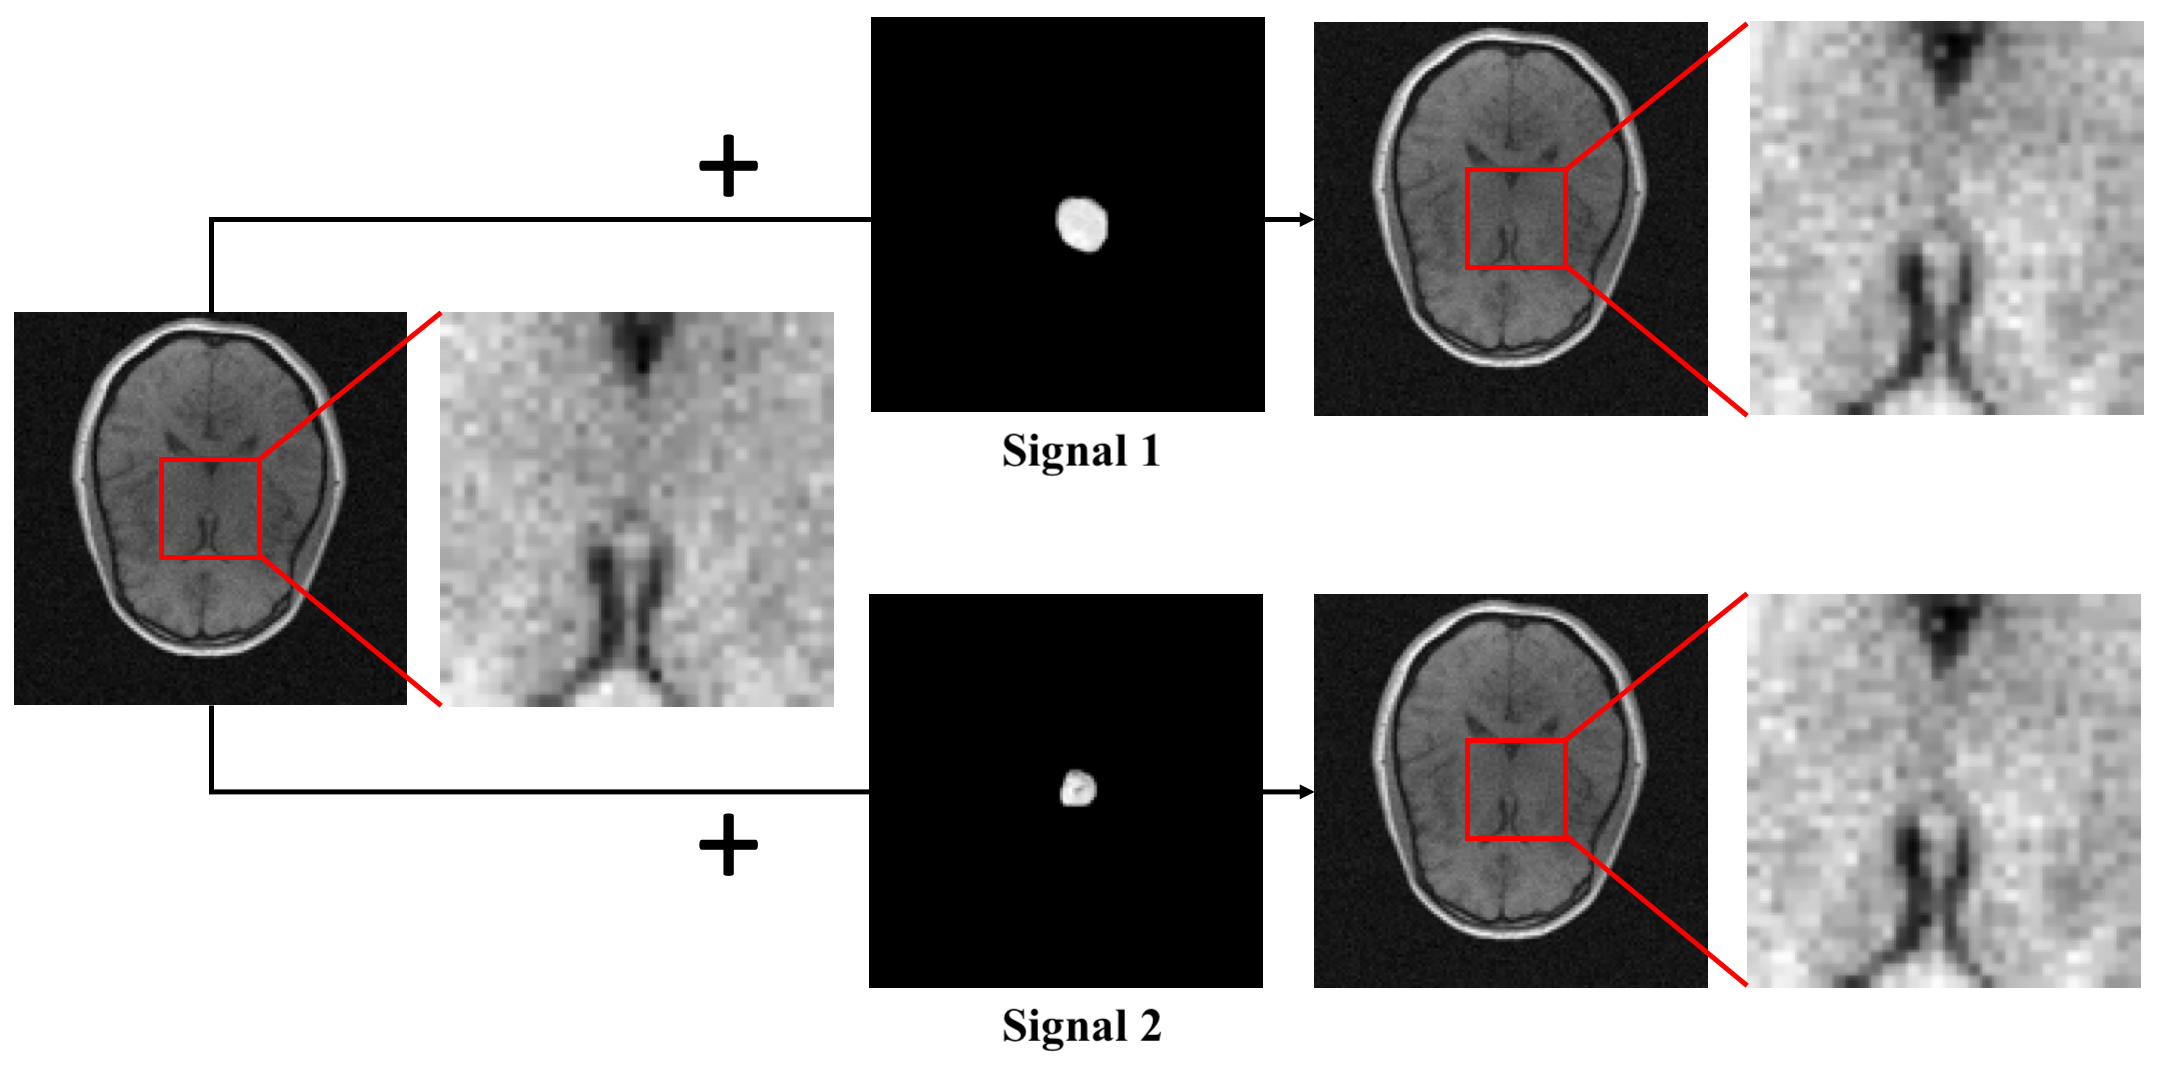

In this work, we propose a novel training strategy named Progressive Growing of AmbientGANs (ProAGANs) to stably train the AmbientGANs for establishing SOMs from noisy and indirect imaging measurements. A MR imaging system that fully samples k-space data was considered: , where denotes a 2D discrete Fourier transform (DFT). The generator in the proposed ProAGAN was trained to synthesize images that depict object properties in the to-be-imaged distribution. However, because the MR imaging system records noisy k-space measurement data, the discriminator cannot be applied directly to distinguish between real and synthetic object images. In our proposed architecture of ProAGAN, a 2D inverse discrete Fourier transform (IDFT) is included in the training of ProAGAN to reconstruct object images from k-space measurements, and the discriminator is trained to distinguish between real and synthetic reconstructed images. The goal is to learn the distribution of images that depict to-be-imaged object properties by progressively training a generator by competing against a discriminator that distinguishes between real and synthetic reconstructed images. This training process is illustrated in Fig. 1.

A simulation study was conducted. MR brain images in the NYU fastMRI Initiative database [11] (https://fastmri.med.nyu.edu/) were employed to form an ensemble of images that depict object properties sampled from the unknown SOM. Specifically, 3000 T1 weighted brain MR images corresponding to the magnetic field strength of 3T were selected, and these 3000 images were resized to the dimension of to be employed as real object images. Fully-sampled MR k-space data of these 3000 object images were simulated, and complex Gaussian noise were added to the k-space data. These 3000 noisy k-space measurement data formed the training dataset. An example of MR brain images, its corresponding k-space measurement data and the reconstructed image (i.e., IDFT of k-space measurement data) are shown in Fig. 2.